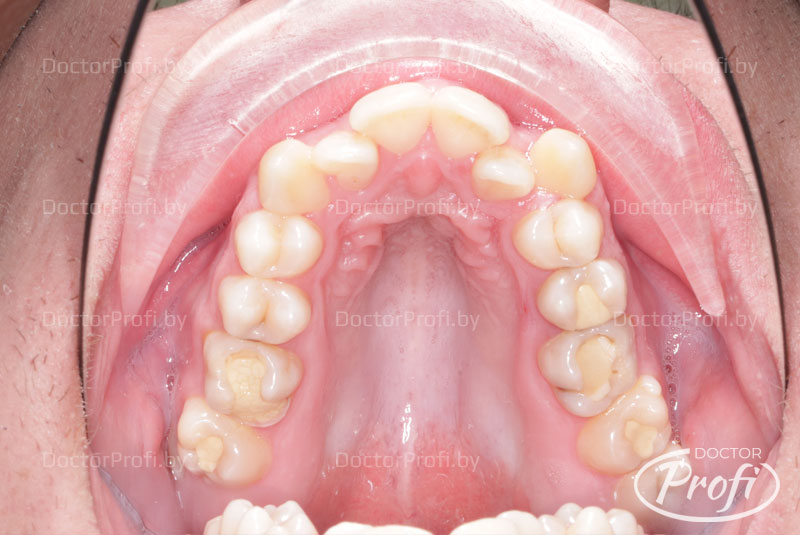

После